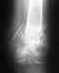

В 1985 и 1986 годах сделаны операции по удалению менисков. Так я прожила 20 лет, родила двоих детей. Имею лишний вес. В 2006 году обратилась с жалобой на свои колени и мне сразу поставлен диагноз деформирующий артроз правого коленного сустава 3-4 степени, левого 2-3 степени. Особенность моя в том, что сильных болей, а поэтому и лечением я не занималась. Но коленные суставы практически потеряла. Сейчас мне 49 лет. Есть направление на эндопротезирование. Но я не знаю, тянуть с операцией (я пока не испытываю сильных неудобств,но пришлось отказаться от высоких каблуков) или операцию нужно делать своевременно, пока суставы в подходящем для операции состоянии, а то когда-то может быть поздно. Спасибо за терпение!